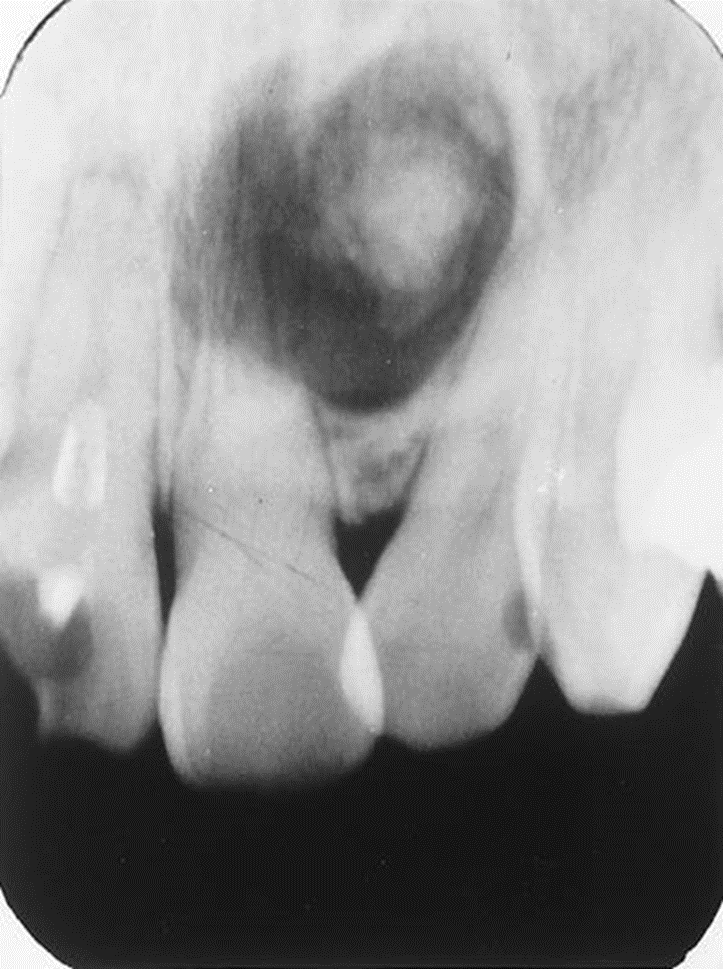

2. Bill is an asymptomatic 47-year-old who presented for routine dental treatment. This radiograph was taken as part of the full mouth survey.

What is your diagnosis?